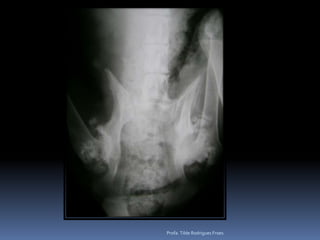

Animal: Cindy, canino, fêmea, 9 anos, Cocker, FC 929/10Suspeita: Pesquisa de metástases – Tumor retal e glândula adeanalProfa. Tilde Rodrigues Froes

Exame radiográfico torácicoCuidados – padrões eventualmente detectados – diferenciação de sua relevância clínicaAspecto radiográfico pulmonarPadrão intersticial  reticular difuso Fibrose senil ObesidadeMetástases (?) – pesquisa-se linfonodos associados – buscar outra técnica diagnóstica por imagemPadrão intersticial nodular (focal o multifocal)Pequenos nódulos – vasos em cortes transversaisOutros diferenciais: degeneração costo-condral, massa externa – mamaria.Pequenos nódulos – 2-4mm – OSTEOMASUsualmente visualizados em animais de grande porte Diferenciar de MetástasesProfa. Tilde Rodrigues Froes

Exame radiográfico torácicoPesquisa de metástasesDiferentes padrõesIntersticial reticularIntersticial reticulonodularIntersticial nodularAlveolar (quando ?)Áreas cavitárias* Considerar sempre as limitações dessa análise* Em gatos* Efusão pleuralProfa. Tilde Rodrigues Froes